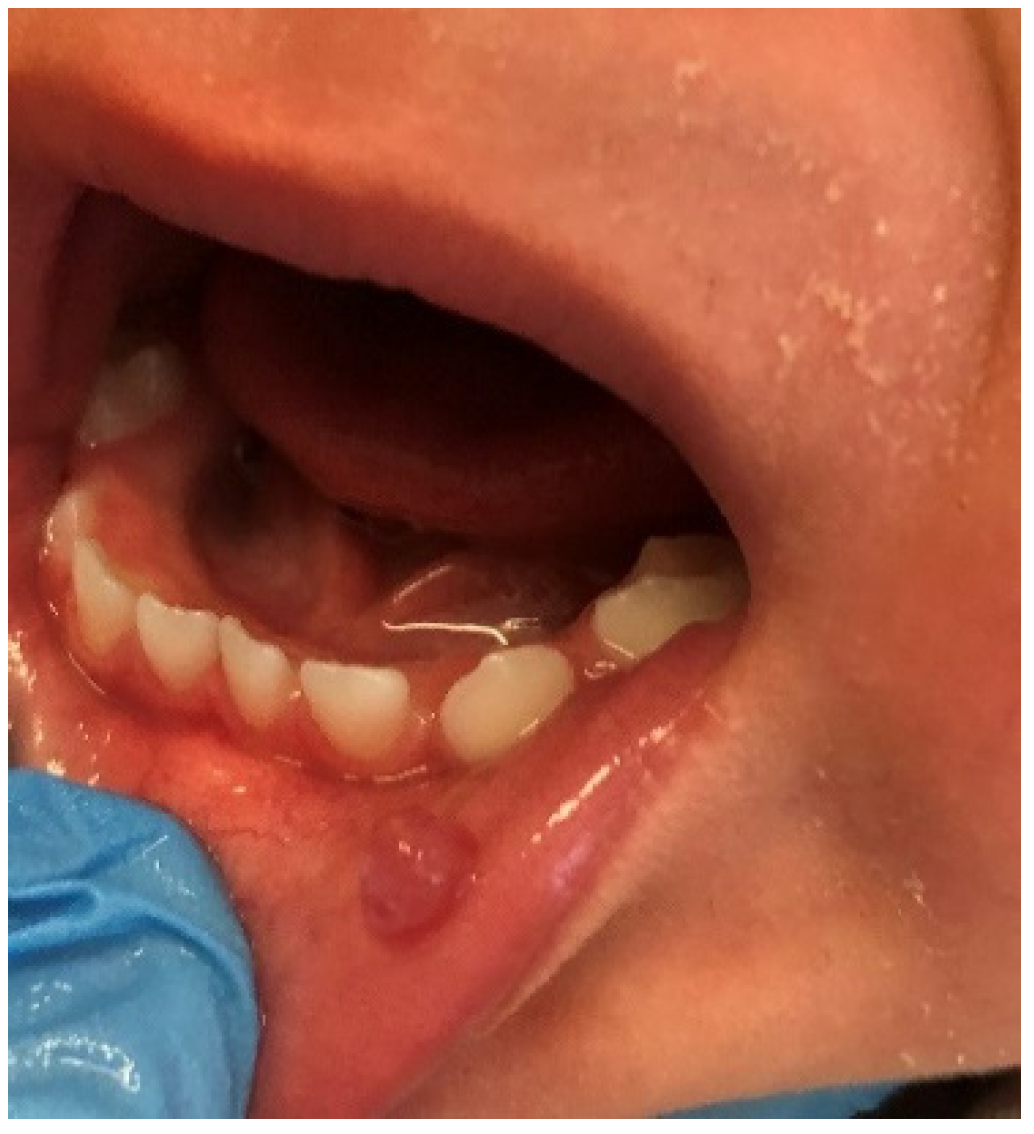

The prevalence of traumatic erosions and ulcers (Figure 11) among pediatric patients varies between studies, from as low as 1.33% up to 17.8%. This may be because the OMLs were classified differently, as certain studies included Morsicatio buccarum in this lesion category [8,9,10,15], while others, like the present study, did not [3,27,28]. In the investigations where MB was included in trauma induced mucosal lesions, its frequency was quite high, 11.8–17.8%, whereases when MB was considered as a separate pathology, the incidence of traumatic erosions and ulcers decreased to the level of 1.33% to 8.53%. In our opinion, it is more accurate to separate these two mucosal pathologies due to their different etiology, characteristics, and method of treatment. In our investigation, the prevalence of traumatic erosions and ulcers was equal in age groups, which confirmed the outcomes of the previous studies [15,27]. While other researchers did not find a gender predilection of this OML, we found a strong and significant correlation between traumatic erosions and ulcers and the male gender (p = 0.03) [8,27].

Figure 11.

Traumatic ulcer on the left buccal mucosa in a school-age boy. Visible in the picture yellow-gray, oval, well-circumscribed ulceration with rolled border. In this case, the lesion resulted from a parafunctional chewing of the cheek due to school stress.